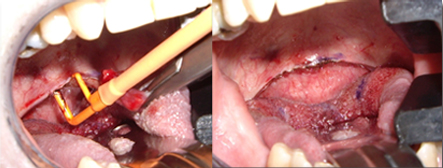

對軟組織切口的比較